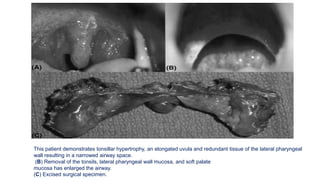

This patient demonstrates tonsillar hypertrophy, an elongated uvula and redundant tissue of the lateral pharyngeal

wall resulting in a narrowed airway space.

(B) Removal of the tonsils, lateral pharyngeal wall mucosa, and soft palate

mucosa has enlarged the airway.

(C) Excised surgical specimen.

This patient demonstratestonsillar hypertrophy, an elongated uvula and redundant tissue of the lateral pharyngeal wall resulting in a narrowed airway space. (B) Removal of the tonsils, lateral pharyngeal wall mucosa, and soft palate mucosa has enlarged the airway. (C) Excised surgical specimen.